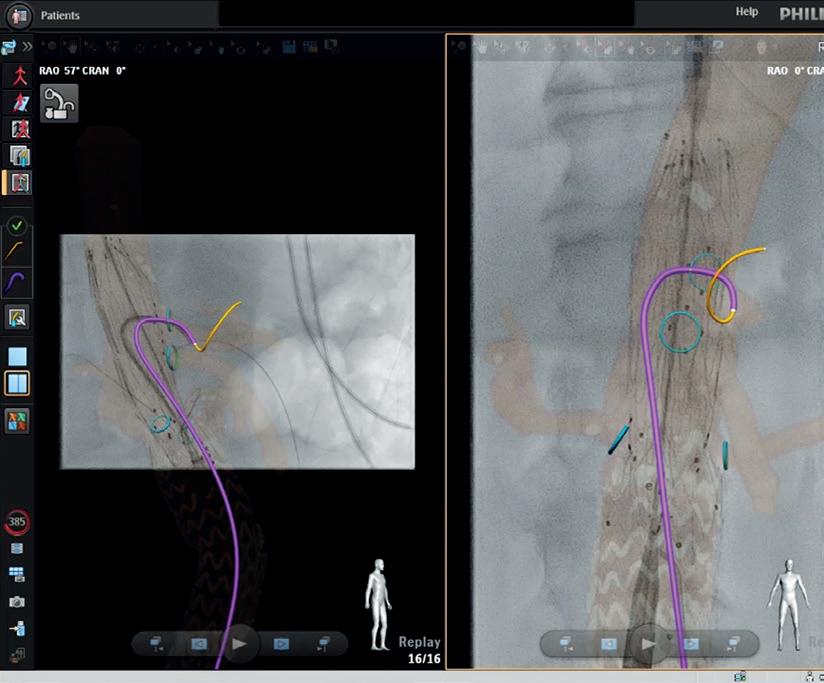

THIS ADVERTORIAL IS SPONSORED BY PHILIPS

Fibre optic technology shows “transformative” potential in endovascular aortic procedures

Two early adopters of Fiber Optic RealShape (FORS; Philips) share their expert opinions on the developing technology, highlighting its future potential in reducing radiation and increasing procedural efficiency.

A “novel way” to visualise and navigate the aorta

Van Herwaarden states that he and two other operators have now performed a combined total of around 150 cases with FORS at the University Medical Center Utrecht. “We are getting used to it,” he says, noting that the team have seen improvements with

For Modarai, fibre optic technology represents a positive addition to his aortic practice. “The fact that you can visualise the catheter and the wire relying on this technology rather than X-ray is a conceptual advance,” he says. The benefits of the technology, in Modarai’s view, are multifactorial, pointing to its potential to protect both the patient and the operator from radiation, whilst also providing a “novel way” to visualise and navigate the aorta. “You get a view of the area that you are navigating in multiple planes,” he explains, “and that in itself also facilitates the procedure, allowing the entire team in the hybrid operating theatre to be able to follow what is going on and to be able to visualise what is being done on the screen”.

the technology in the three years since they started using it. He mentions that with the recent introduction of Philips’ 3D Hub technology, for example, it is possible to use many different commercially available catheters and show them with the FORS technology.

The team now use FORS weekly and in “almost all endovascular aneurysm repairs,” van Herwaarden details. Specifically, he tells Vascular News that FORS “really gives you a better understanding of the position and 3D morphology of the devices in the 3D anatomy or workspace,” noting that the better view the technology provides makes cannulations easier.

According to van Herwaarden, the future of FORS lies also in its combined use with other emerging technologies, for instance robotic tracking, artificial intelligence, and intravascular ultrasound (IVUS), with the combination offering “an even greater promise for simplifying complex procedures and realising radiation dose reduction for patients and for staff”.

Modarai believes the technology will be “transformative” in endovascular aortic procedures, while adding the caveat that there is still some way to go. He looks ahead to iterative improvements with regard to compatible wires and catheters, and the footprint of the ancillary devices, for example, which will make fibre optics “easier and easier” to incorporate into clinical practice. Eventually, he hopes, it will become an “essential” part of the workflow, allowing operators to circumvent the use of X-rays for endovascular procedures. “When that goal is reached, then it is difficult to imagine that one would want to perform these procedures without a technology like this.”

L-R: Bijan Modarai conducting a FORS case (image courtesy of Guy’s and St Thomas’); Cannulation of the coeliac trunk in fenestrated endovascular aneurysm repair (image courtesy of UMC Utrecht). Bijan Modarai Joost van Herwaarden